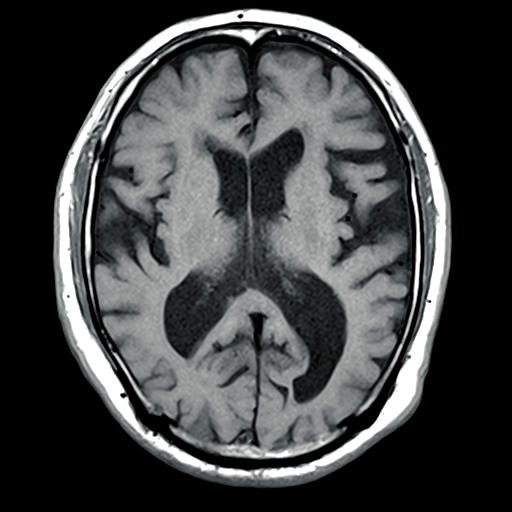

2)MRIでの水頭症の鑑別

MRIで撮影すると、T1強調像では図1-3のように描写され、CTと比較してより鮮明に脳室やくも膜下腔が拡大していることがわかります。T2強調像では図1-4のように描写され、脳室周辺の脳浮腫を認めています。

●T1強調像では、髄液は黒く映る( 低信号域)

●T2強調像では、髄液は白く映る(高信号域)